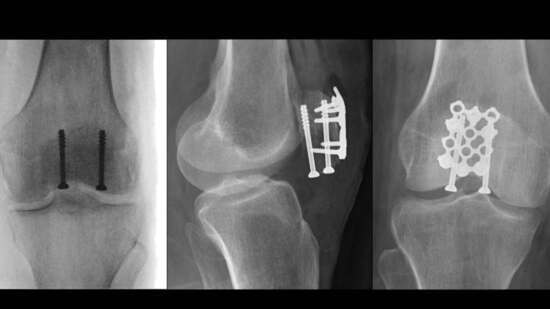

![]() Kneecap Fractures (Patella Fractures): Fixation With Screws and Braided Suture Animation 1m  |

![]() Kneecap Fractures (Patella Fractures): Fixation With a Plate and Screws Animation 1m  |

Kneecap Fractures (Patella Fractures): Fixation With a Plate and Braided Suture